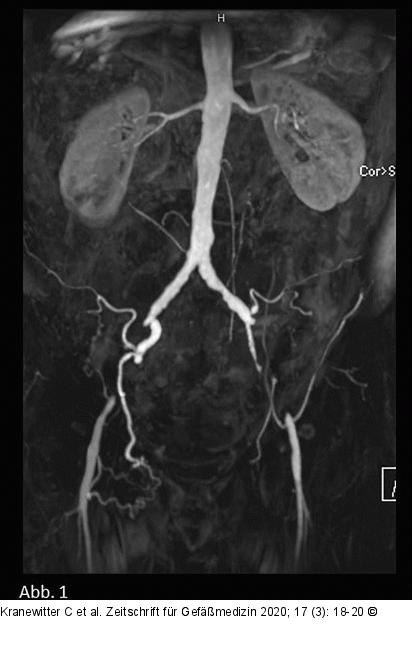

Abbildung 1: MIP - MRA Die Maximumintensitätsprojektion (MIP) der MRA zeigt einen kompletten Verschluss der AIE beidseits auf einer Länge von 6 cm rechts und 7 cm links. Die AFC beidseits regelrecht. |

Die Maximumintensitätsprojektion (MIP) der MRA zeigt einen kompletten Verschluss der AIE beidseits auf einer Länge von 6 cm rechts und 7 cm links. Die AFC beidseits regelrecht. |